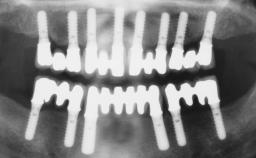

Immediate Loading of Six Implants in the Maxilla and Final Restoration with a Full-Arch CAD/CAM Zirconia FDP

# of Implants 6

Type of Implants One-Piece

Bone Augmentation Horizontal|Simultaneous